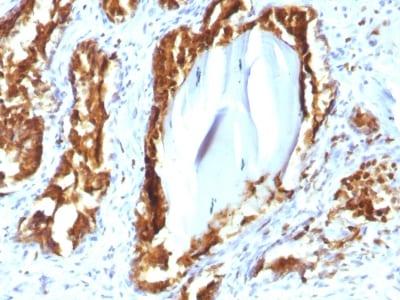

This antibody recognizes a protein of 52 kDa, identified as prostate specific acid phosphatase (PSAP). This enzyme catalyzes the conversion of orthophosphoric monoester to alcohol and orthophosphate. It is synthesized under androgen regulation and is secreted by the epithelial cells of the prostate gland. PSAP is found in non-neoplastic adult and fetal prostatic glands, primary and metastatic prostatic carcinomas. It shows no staining in granulocytes, osteoclasts, parietal cells of the stomach, liver cells, renal cell or breast carcinomas.Primary antibodies are available purified, or with a selection of fluorescent CF® Dyes and other labels. CF® Dyes offer exceptional brightness and photostability. Note: Conjugates of blue fluorescent dyes like CF®405S and CF®405M are not recommended for detecting low abundance targets, because blue dyes have lower fluorescence and can give higher non-specific background than other dye colors.

Positive Control

PC12 cells or normal prostate or prostate carcinoma

IHC, FFPE (verified)

IHC (FFPE) (verified)

Higher concentration may be required for direct detection using primary antibody conjugates than for indirect detection with secondary antibody|Immunohistology (formalin): 0.5-1.0 ug/mL for 30 minutes at RT|Staining of formalin-fixed tissues requires boiling tissue sections in 10 mM citrate buffer, pH 6.0, for 10-20 minutes followed by cooling at RT for 20 minutes|Optimal dilution for a specific application should be determined by user